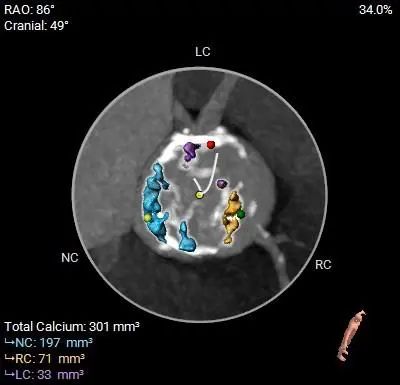

TYPE-1型二叶式主动脉瓣,中重度钙化,钙化分布不均匀,主要分布在瓣叶及管壁附着缘上,瓣膜锚定力可,左冠瓣和右冠瓣之间有纤维融合,流出道呈直筒型。

左右冠开口高度尚可,左侧冠脉切线位瓣叶长度<冠脉开口上缘到瓣叶附着缘距离,右侧冠脉切线位瓣叶长度<冠脉开口下缘到瓣叶附着缘距离,左侧前降支及右侧冠脉有钙化分布。

钙化预览

本例患者术前有心绞痛、心衰症状,心脏彩超提示主动脉瓣重度狭窄伴轻度返流,患者因年龄大,基础疾病较多,拒绝外科开胸手术,术前超声评估:主动脉最大流速 5.89m/s,平均压差:84mmHg,有TAVR手术指征。术前CT分析提示患者为Type 1 型二叶式主动脉瓣,L-R间纤维融合嵴,瓣叶增厚伴轻中度钙化,存在一定瓣膜位移及瓣周漏风险;患者CT测量左侧冠脉切线位瓣叶长度<冠脉开口上缘到瓣叶附着缘距离,右侧冠脉切线位瓣叶长度<冠脉开口下缘到瓣叶附着缘距离,左侧前降支及右侧冠脉有钙化分布。